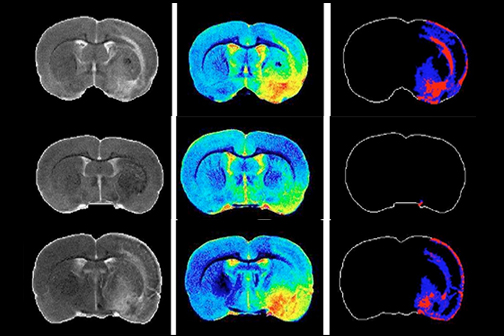

LSU Health New Orleans Discovery May Complement Recovery from Ischemic Stroke

A study led by Nicolas Bazan, MD, PhD, Director of the LSU Health New Orleans Neuroscience Center, pinpointed which cells within specific areas of the brain are involved in post-stroke response and found that the delivery of precursors of Elovanoids, a class of molecules that synchronize cell-to-cell communication and neuroinflammation/immune activity in response to injury, improved neurological deficit in an experimental model of ischemic stroke. More

LSU Health New Orleans Study Identifies a Potential New Approach to PTSD Treatment

An LSU Health New Orleans research study led by Siqiong June Liu, PhD, Professor of Cell Biology and Anatomy, has found that cerebellar inhibitory interneurons are essential for fear memory, a type of emotional memory formation. Inhibitory interneurons within the cerebellar circuitry act as gatekeepers and control the output of the cerebellar cortex. The formation of fear memory requires the activity of these interneurons. The findings, which may lead to a novel treatment approach for post-traumatic stress disorder, are published in Cell Reports. More